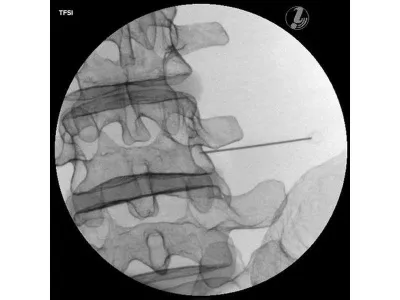

Тренажер для спинальных инъекций с визуальным контролем

Тренажер для инъекций в поясничный отдел с визуальным контролем позволяет повысить процент успешных результатов при медицинском вмешательстве на позвоночнике путем использования стандартизированного обучения выполнению инъекций.

- Трансфораминальная эпидуральная инъекция стероидов (TFSI)